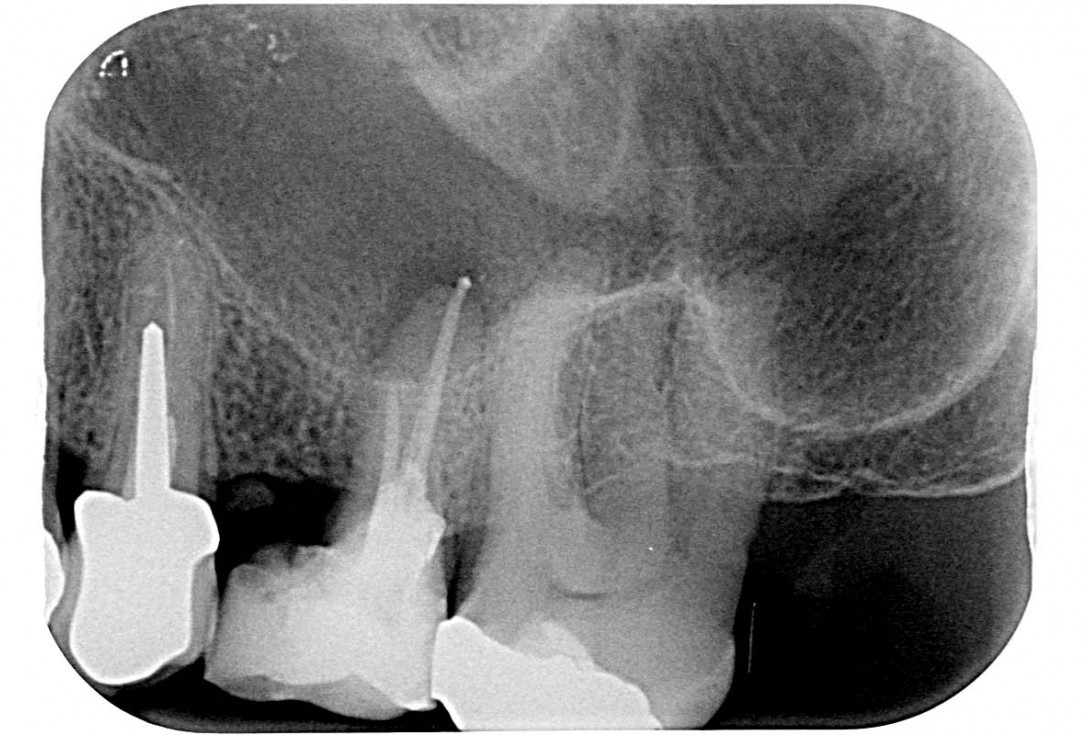

01/35 - Initial x-ray, tooth 25 compromised and to be extractedMaxillary sinus cyst removal using the Crocodile Technique and subsequent lateral sinus lift - Dres. C. Scognamiglio and A. Perucchi